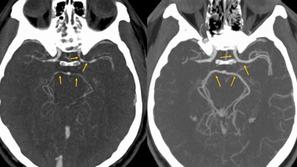

Zožitev arterij Čili: Po zaužitju popularne zelenjave so ga odpeljali na urgenco Računalniška tomografija glave pokazala, da so se moškemu močno zožile arterije.